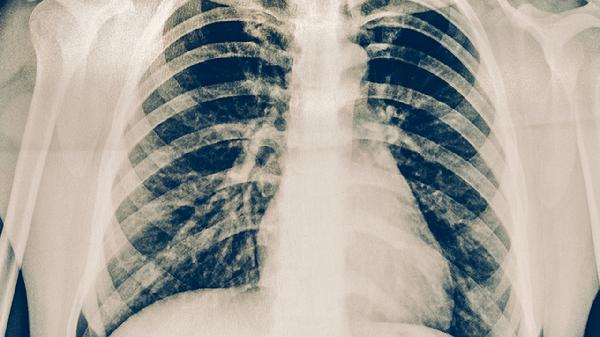

与普通肺结核相比,耐多药肺结核的病理过程更为复杂。其肺部病灶往往更广泛,容易出现空洞,组织破坏严重。细菌学上,痰涂片和培养持续阳性的时间长,治疗过程中菌阴转慢。疾病进展更快,肺内播散和肺外结核的发生概率也相对更高。